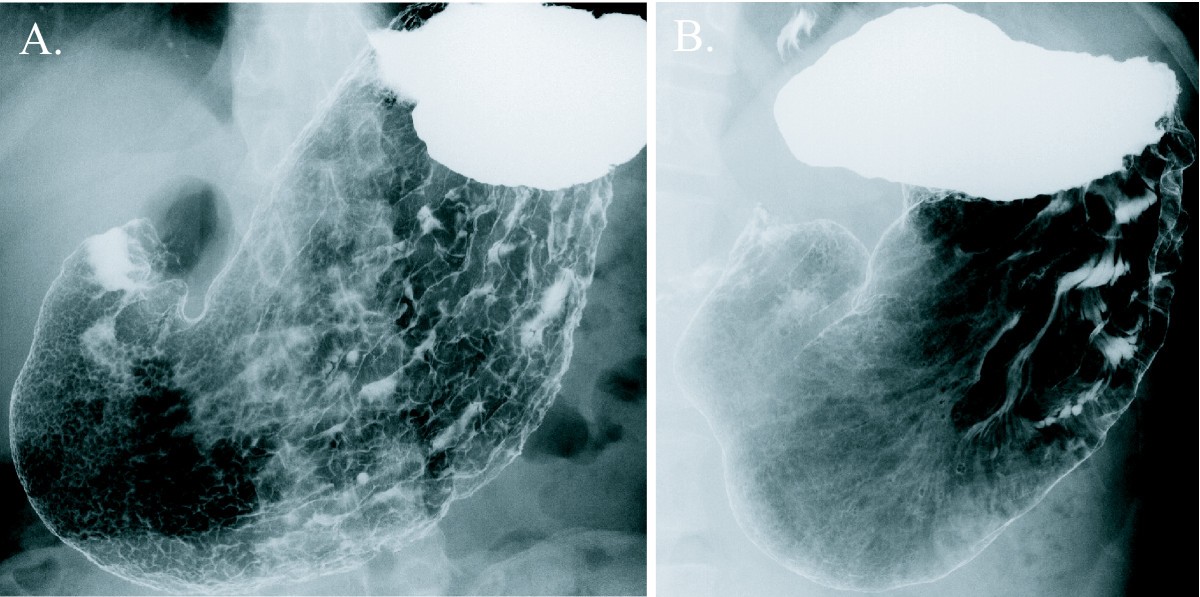

Gastritis is an inflammation, irritation, or erosion of the lining of the stomachit can occur suddenly (acute) or gradually (chronic) what causes gastritis? gastritis can be caused by irritation. Gerd chronic gastritis. Gastritis melibatkan sekelompok kondisi yang menyebabkan peradangan pada lapisan lambung gejala gastritis mirip dengan gejala gerd di mana ada rasa sakit terbakar atau gangguan pencernaan mari sedikit membahas tentang anatomi tubuh agar dapat membantu menjelaskan perbedaan antara gastritis dan gerd.

Chronic gastritis and gerd i've done 2 endoscopies and both come out with active chronic gastritis and nothing else, i don't have the pylori bacteria anymore i dont have heartburn but i have lots of burping, feeling that i always have something in my throat and excessive throat clearing. By definition gastritis is inflammation of the stomach lining (gastro = stomach, it is = inflammation). for years, i thought gastritis and reflux (gerd) were pretty much the same thing. recently thoug. Chronic gastritis. your stomach lining, or mucosa, has glands that produce stomach acid and other important compounds. one example is the enzyme pepsin..